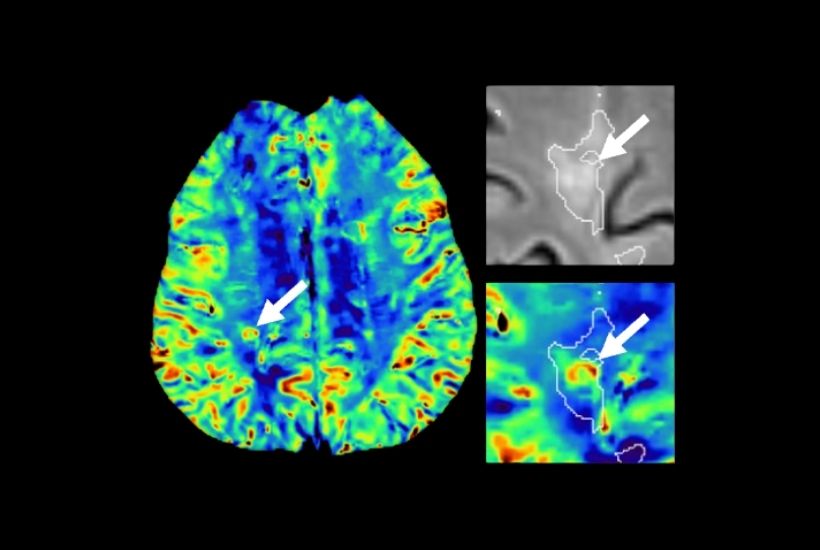

INRIA x CHU RENNES

MULTIPLE SCLEROSIS

Objectives and results

A better understanding of brain and spinal cord injuries :

- signs of the paramagnetic halo and central vein: inflammatory mechanisms

- magnetism of the myelin sheath